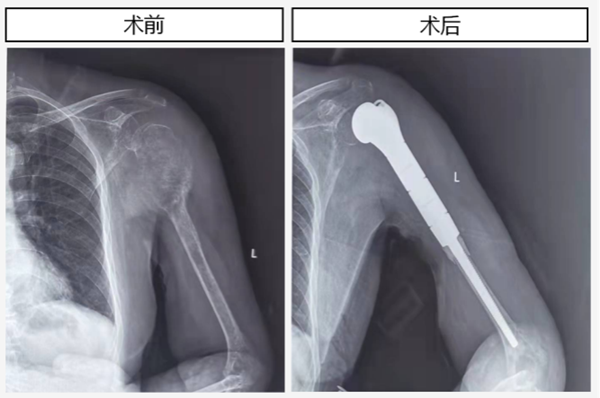

近日,骨一科成功完成一例“左侧肱骨近端巨大转移性肿瘤”导致的肱骨近端严重骨破坏伴病理性骨折的人工肱骨头置换术和肩袖重建术,术后患者恢复了肩关节结构及功能。

患者是一名73岁的女性,既往因中度-重度绒毛管状腺瘤行直肠肿瘤根治切除术。2个月前患者无明显诱因出现左上肢剧烈疼痛,伴外展功能障碍,严重影响患者夜间休息及日常生活,就诊于多家医院及骨科医院,给与镇痛、理疗等治疗,疼痛症状未见明显好转。2周前患者左侧肩关节疼痛较前加重,为求进一步诊治遂来我院,在骨一科倪建龙主治医师仔细问诊,行X线片提示左侧肱骨近端占位伴病理性骨折,通过结合病人病史、查体及肿瘤标记物、全身骨显像、病理活检等一系列辅助检查,排除了原发性肱骨肿瘤,考虑为左侧肱骨近端巨大转移性肿瘤导致的肱骨近端骨质破坏伴骨折。

转移性肱骨近端肿瘤位于重要血管、神经密布的左侧肩关节,术中彻底切除损毁的骨质并恢复肩关节功能困难重重。面对挑战,在党晓谦主任的全程指导下,术前给予系统治疗。术前测量患者左侧肱骨全长28cm,通过与工程师多次协商,精密计划,决定采用肿瘤型人工肱骨假体。2022年03月17日由时志斌主任医师带领团队在麻醉及手术室协助下,为患者顺利施行左侧肱骨肿瘤切除术、人工肱骨头置换术及肩袖重建术。术中探查发现左侧肱骨膨大肿物体积约10.0cm×7.0cm×5.0cm,肿瘤侵入肱骨近端肩袖止点,并有病理性肱骨骨折。因为肩袖、肱二头肌长头、胸大肌及三角肌起止点均毗邻肱骨肿瘤,且附近周围神经及血管密布,瘤段切除极其困难。经过2个半小时的奋战,完整切除转移性肿瘤破坏的肱骨瘤段,并植入长17cm的左侧人工肱骨头及假体柄,继而附着并固定左侧肩袖、胸大肌肱骨止点、肱二头肌长头肌腱止点及三角肌止点。术后病理回报:左肱骨转移性腺癌,形态支持消化道来源。骨一科成功为复杂骨转移肿瘤患者实施保肢手术,术后患者规律戴支具并接受专业康复训练,并请肿瘤科协助制定术后用药治疗方案,解决了患者的疼痛,避免截肢。